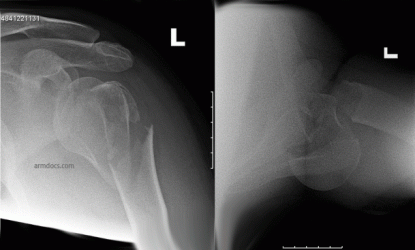

The operation is performed to treat selected fractures of the proximal humerus, which are significantly displaced or associated with a dislocation. In some individuals surgery may be offered in order to allow an earlier return to function.

Proximal Humerus Fracture 2A

Before